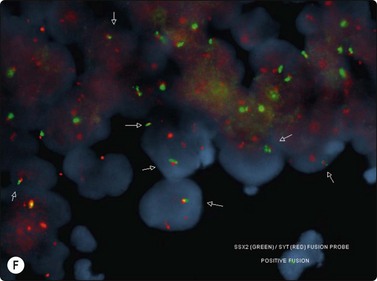

Other neoplasms

The most common sarcomas of this site include malignant fibrous histiocytoma and liposarcoma.131,132 Synovial sarcoma is well described.133 We have seen a single case of monophasic synovial sarcoma of mediastinum diagnosed on transoesophageal EUS FNB by the demonstration of SYT-SSX fusion transcripts by FISH on cell blocks, indicating X:18 translocation (all material shown here is courtesy of Dr. Anita Soma, PathWest QE II AP). (Fig. 9.10) The patient was a 45-year-old male with an 11-cm mass adjacent to the lower oesophagus, displacing the heart. Smears showed a rather bland spindle cell population but with mitotic activity. The cell block immunohistochemistry was negative for cytokeratins, CD117 and smooth muscle markers, making leiomyosarcoma and GIST unlikely. The tumor did show positive staining for CD99, BCL2 and CD34, raising the possibility of solitary fibrous tumor or synovial sarcoma. An SYT-SSX1 fusion transcript was detected by reverse transcriptase PCR, reinforcing the FISH cytogenetics. No other diagnostic procedures were undertaken (Fig 9.10).

image image image image image image image

Fig. 9.10 Synovial sarcoma

(A) Large infiltrative mass posterior to heart (Thoracic CT); (B) Loose fascicle of spindle cells including small blood vessels. Background of bare tumor nuclei (H&E, LP); (C) Loose cluster of bland spindle cells but with mitotic activity (H&E, HP); (D) Cell block, small spindle tumor cells with non-specific features (H&E, HP);(E) FISH on cell block, breakapart probe for SYT showing positive disruption of red-green-yellow components (FISH, HP); (F) FISH on cell block, fusion probe for SSX2 (green) and SYT (red) probes showing positive fusion of green and red components. (FISH, HP); (G) FISH on cell block, fusion probe for SSX2 (green) and SYT (red) probes showing positive fusion of green and red components (FISH, HP).